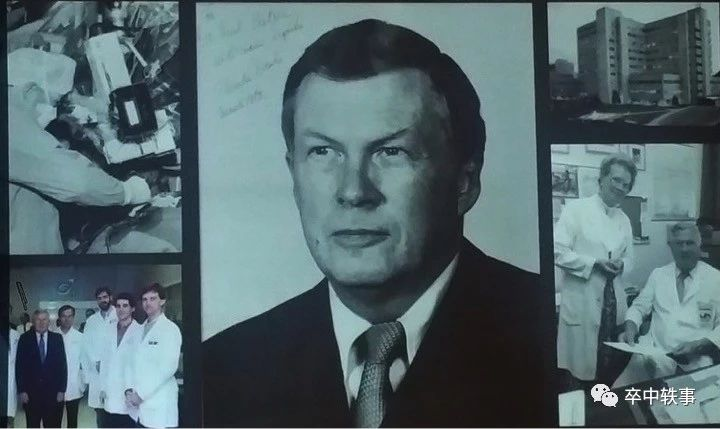

Charles George Drake(1920-1998,上图)是加拿大神经外科医生,以研究脑动脉瘤而留名于世。

Drake(上图)生于加拿大的安大略省,1944年在西安大略大学 - The University of Western Ontario 医学院毕业。

Drake(上图)获得了 American Association of Neurological Surgeons 的 Harvey Cushing 奖。

Drake(上图左,与 Sydney Peerless 讨论病例,右,Drake 在手术中)通过这个院中院培养了多名学术型神经外科医生,后人称之 “Drake 神经外科学院 - The Drake School of Neurosurgery”。

Drake(上图中)出身贫寒,在他出生前3个月 Drake 的父亲就因流感去世了,9岁时母亲改嫁,他在两个姑姑的照顾下长大。Drake 从小打工挣零花钱,高中毕业后打算进工厂工作,但是他的生物老师劝他去上大学。

与 Ruth Pitts 结婚后,生了4个儿子,后来有了14个孙辈。Drake 的二儿子 James Drake(上图)跟随了他的脚步,成了一名儿科神外医生。